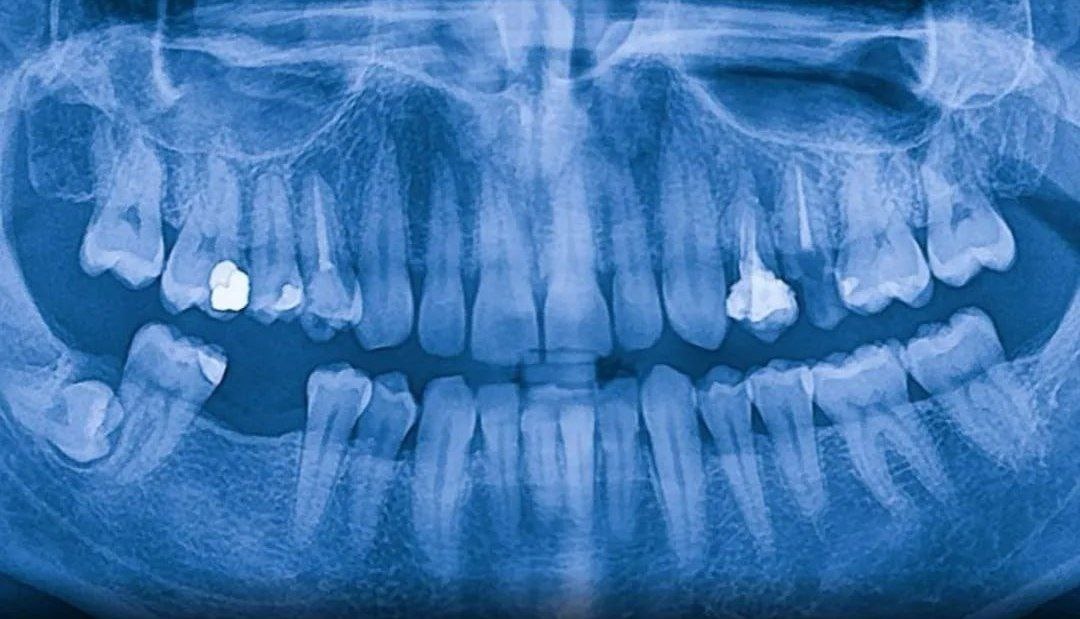

Вот это – зуб. Вы когда-нибудь задумывались, каково было бы, если бы вы могли бесконечно отращивать новые зубы, как акула, или просто как человек, который не хочет носить протезы? Летом 2024 года японская биотехнологическая компания Toregem Biopharma начнет клинические испытания препарата, который позволит именно это. Вы, вероятно, помните, как в детстве теряли молочные зубы, а затем, к счастью, у вас росли постоянные. Однако ваше тело могло бы продолжать выращивать новые зубы, но оно вырабатывает белки, которые останавливают этот процесс после прорезывания постоянных зубов. Новое лечение заблокирует ген, ответственный за выработку этих белков, так что, теоретически, вы сможете отращивать новые зубы снова и снова. Если метод окажется эффективным, он может заменить зубные протезы и импланты. Если же он не сработает, то вы, возможно, превратитесь в нечто вроде мутанта-акулы с бесконечными рядами пугающих зубов… Какой-нибудь монстр. В любом случае, вы победитель. Во втором варианте у вас

Вот это – зуб. Вы когда-нибудь задумывались, каково было бы, если бы вы могли бесконечно отращивать новые зубы, как акула, или просто как человек, который не хочет носить протезы?